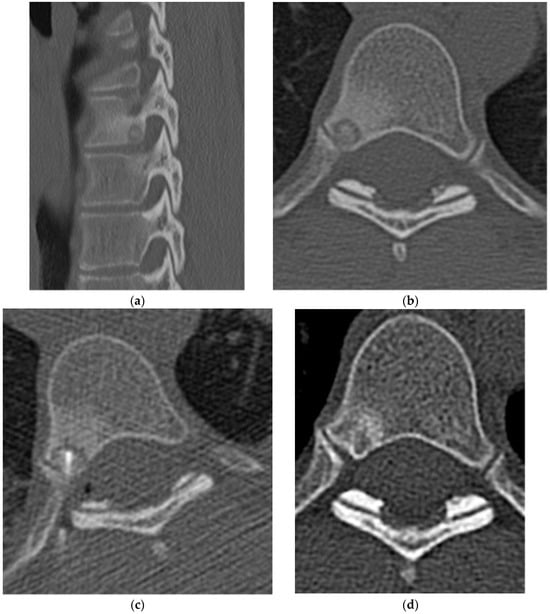

2.1.2. Osteoid Osteoma

2.1.3. Osteoblastoma